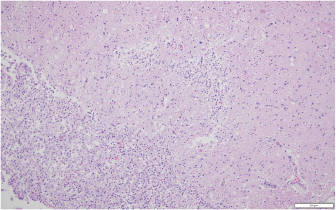

Within the brain, there was subacute to chronic, multifocal to coalescing, severe, granulomatous, lymphoplasmacytic, and neutrophilic meningoencephalitis predominantly of the right telencephalon and diencephalon associated with arteritis and arterial thrombosis of the right cerebral artery. Moderate chronic multifocal encephalomalacia was present bilaterally within the rostral cerebrum (Fig. 6). Numerous intralesional hyphae were identified in all lesions. Culture yielded a hyphal organism with morphologic features consistent with an oomycete, and PCR sequencing was consistent with the previously obtained L. giganteum isolate from this dog.

Fig. 6. Representative example of granulomatous encephalomalacia affecting the gray matter of the right cerebrum (HE staining), 100×. There were large numbers of macrophages, lymphocytes, plasma cells, fewer multinucleated giant cells, and scattered neutrophils within and surrounding areas of necrosis.